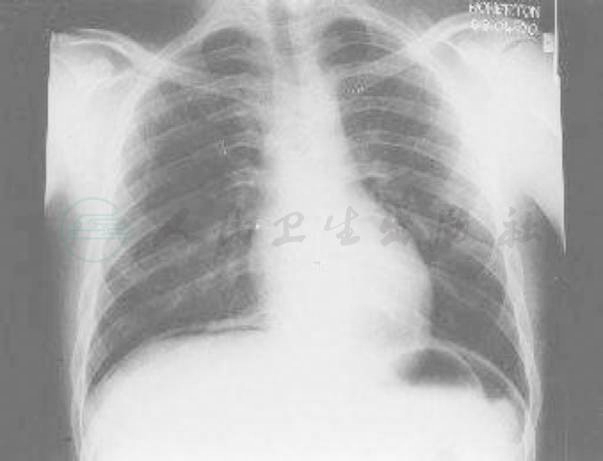

立位腹部平片:膈下见游离气体影。考虑消化道穿孔(图1)。

图1 立位腹部平片